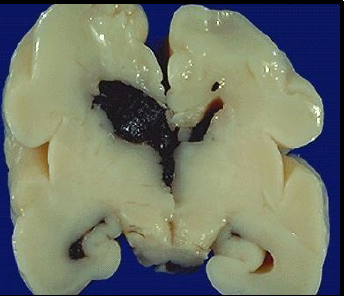

hydrancephaly

cerebral hemispheres are absent; brain is filled with CSF within sacs

premature (vasculature strength greatly increases in the last 10 weeks)

what makes babies more susceptible to intraventricular hemorrhage?